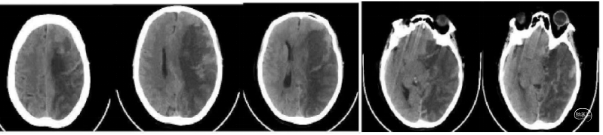

术后CT检查:造影剂外渗。

术后1小时左下肢肌力2级,问答基本切题,言语流畅。

术后8小时出现意识不清,CT示脑水肿明显,给予去骨辨减压重症监护笫3天呈浅昏迷,双下肢肌力3级。第5天,病情加重,预后不良。